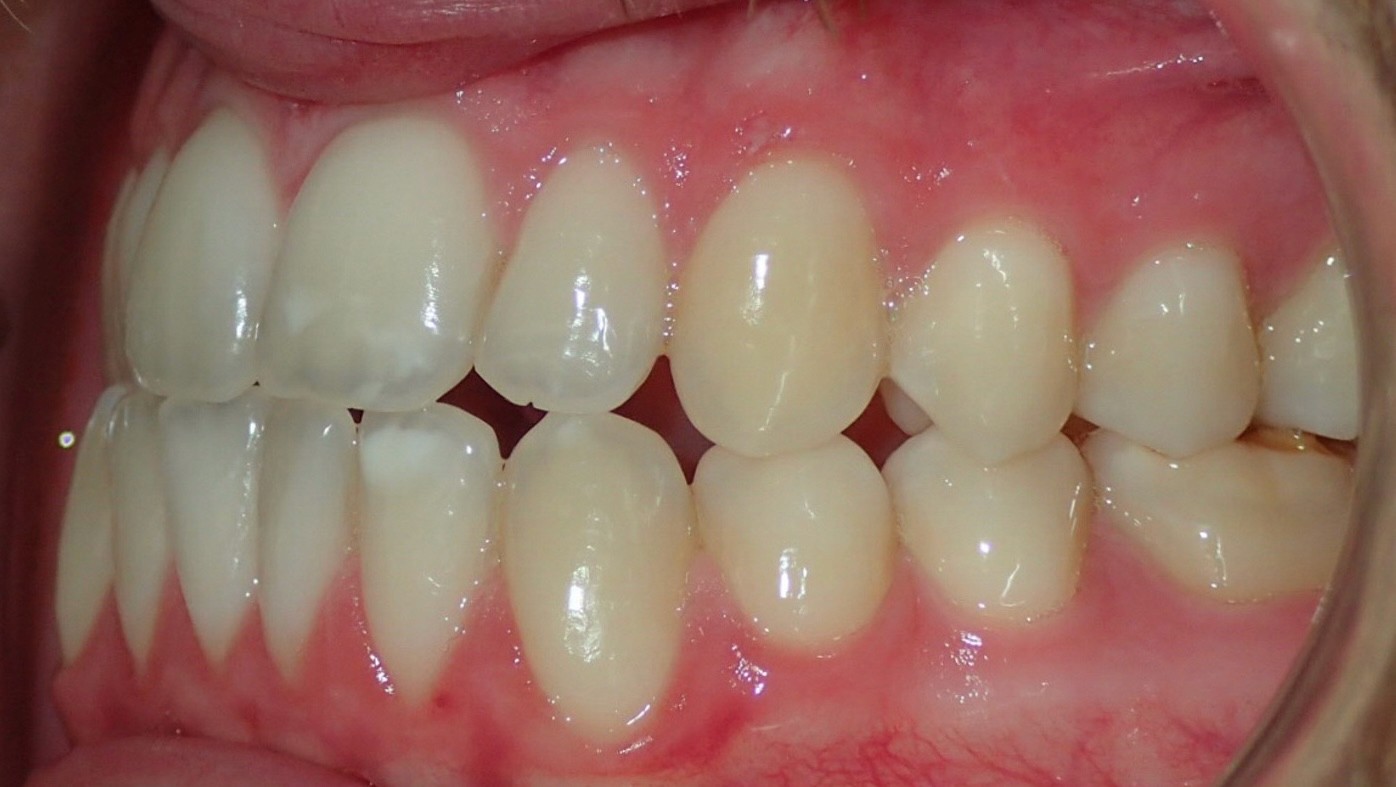

Diagnosis: Class III malocclusion, edge-to-edge anterior relationship, lower anterior crowding

Initial treatment

INTRAORAL